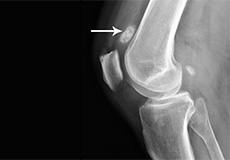

Loose Bodies in the Knee

Loose bodies are fragments of detached cartilage or bone inside the knee joint. These fragments may be free floating (unstable) or may be trapped (stable) within the joint.